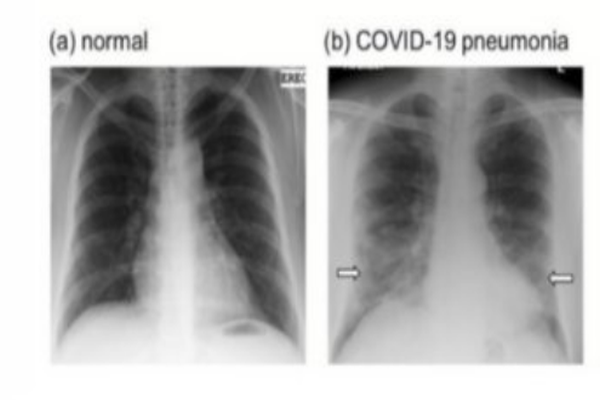

Влијанието на ковид-19 врз белите дробови

Вирусот САРС-КоВ-2 во многу случаи е насочен кон респираторниот систем, што доведува до воспаление на белите дробови. Во тешки случаи може да дојде до хипоксемија, што е водечка причина за смрт кај ковид-пациентите.